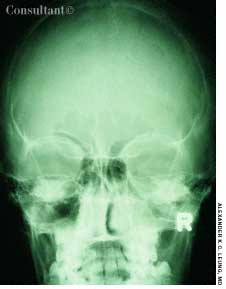

A 29-year-old woman is brought to the emergency department after a caraccident. She complains of head pain and has a contusion over the posterioraspect of the right temporal bone and right occipital bone; a small amount ofblood flows from the right external auditory canal. She has only a vague recollectionof the accident. Past medical history-although difficult to ascertain-seems noncontributory.